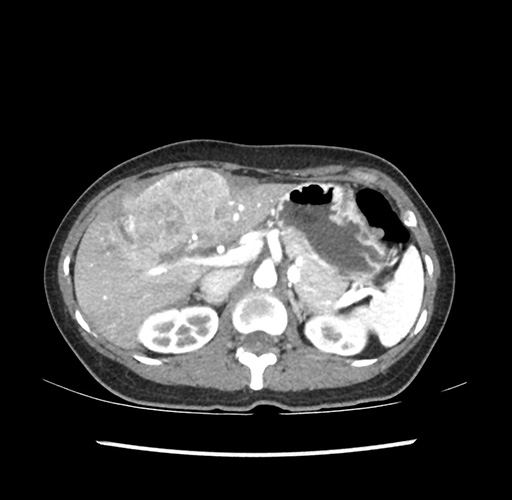

Imaging Analysis

Look through the patient's CT scan to identify any areas of concern for the necessary procedure.

Based on your CT findings, which issue(s) would give reason for "planned slowing down moment(s)" in this case?